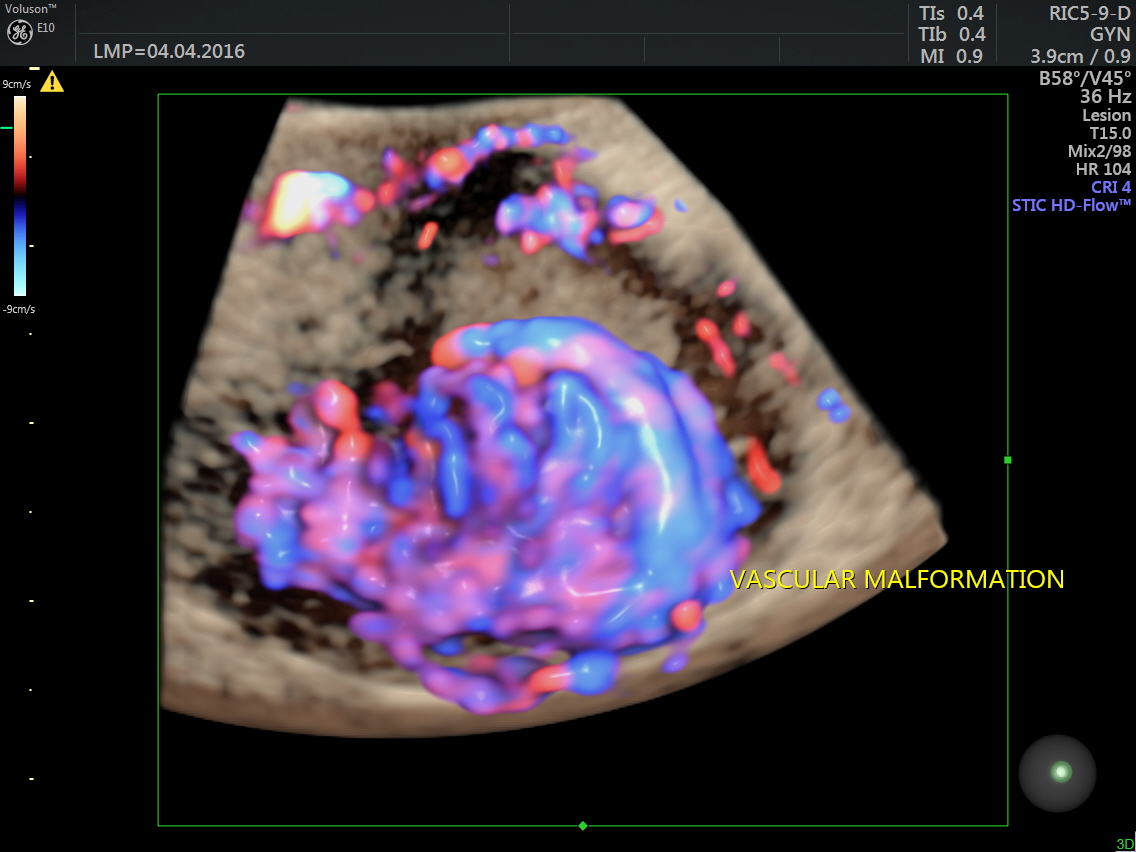

Power Doppler reconstruction images of trans-abdominal scan are given below

The following are the different sections of the Power Doppler reconstruction images of the trans-vaginal scan.

The following are the reconstructed 3D Power Doppler images.

The ultrasound diagnosis was a vascular malformation in the uterus .She was referred to an interventional radiologist,who did a CECT the next day.